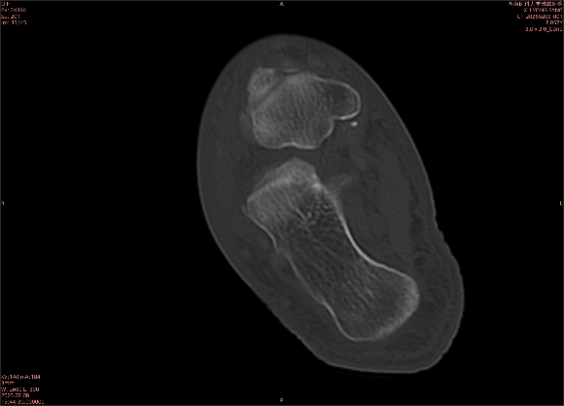

舉例圖像

圖1

專業(yè)解釋看不懂沒關(guān)系,大家看圖1和圖2就可以了,這是同一個(gè)患者跟骨的磁共振和CT圖像,圖1的紅色箭頭指示的黑線就是磁共振圖像顯示的骨折線,一目了然。而對(duì)比圖2的CT圖像上并未顯示異常。